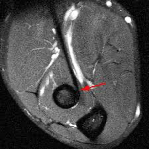

Coronal:

(Courtesy: Supermedica.com) |